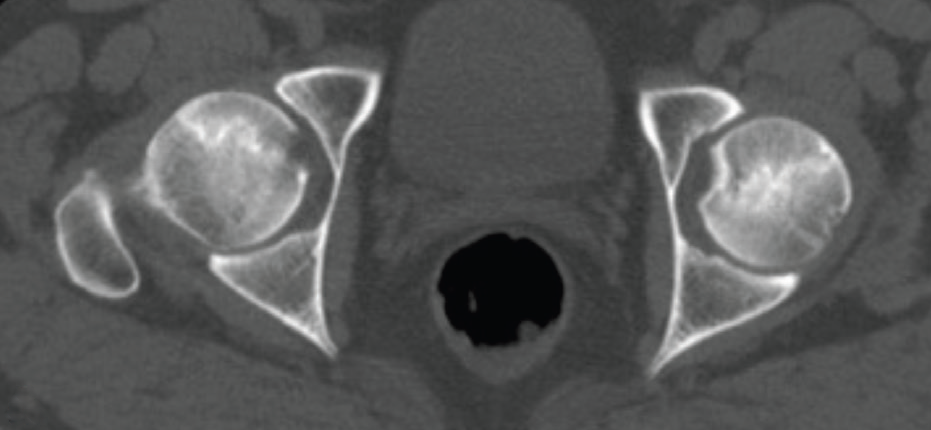

Bilgisayarlı Tomografi (BT): BT taramaları, kemik içindeki değişiklikleri ayrıntılı bir şekilde gösterdiğinden özellikle cerrahi planlamada kullanılır.